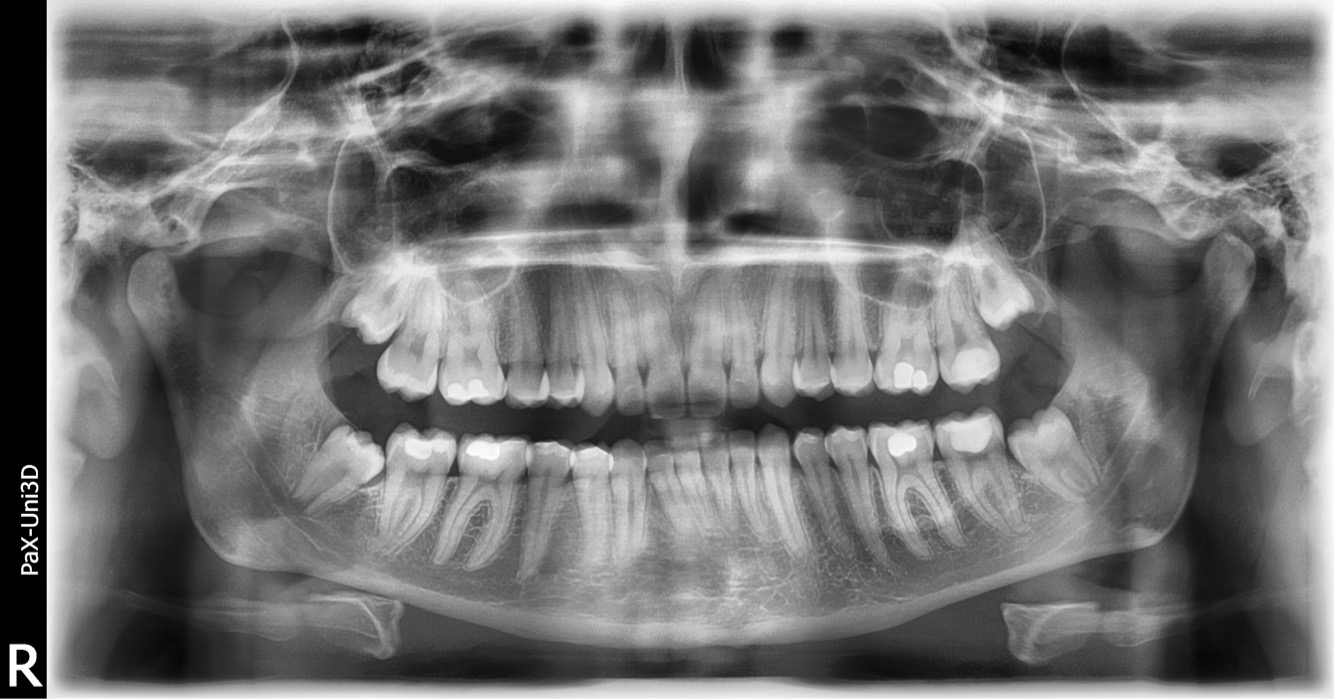

In allegato Il dente in questione è il secondo molare a partire da destra in basso, quello che si vede più riempito.

IL " Granuloma " è' un' infezione cronica dell' apice di una radice derivante da svariate cause che comunque hanno determinato tutte la necrosi della polpa dentaria ( nervo ) . Si manifesta nella radiografia dentale come una perdita di sostanza ossea iattorno all' apice della radice interessata . ( zona radio logicamente più scura rispetto al resto del tessuto osseo che diviene francamente nera quando evolve in cisti .